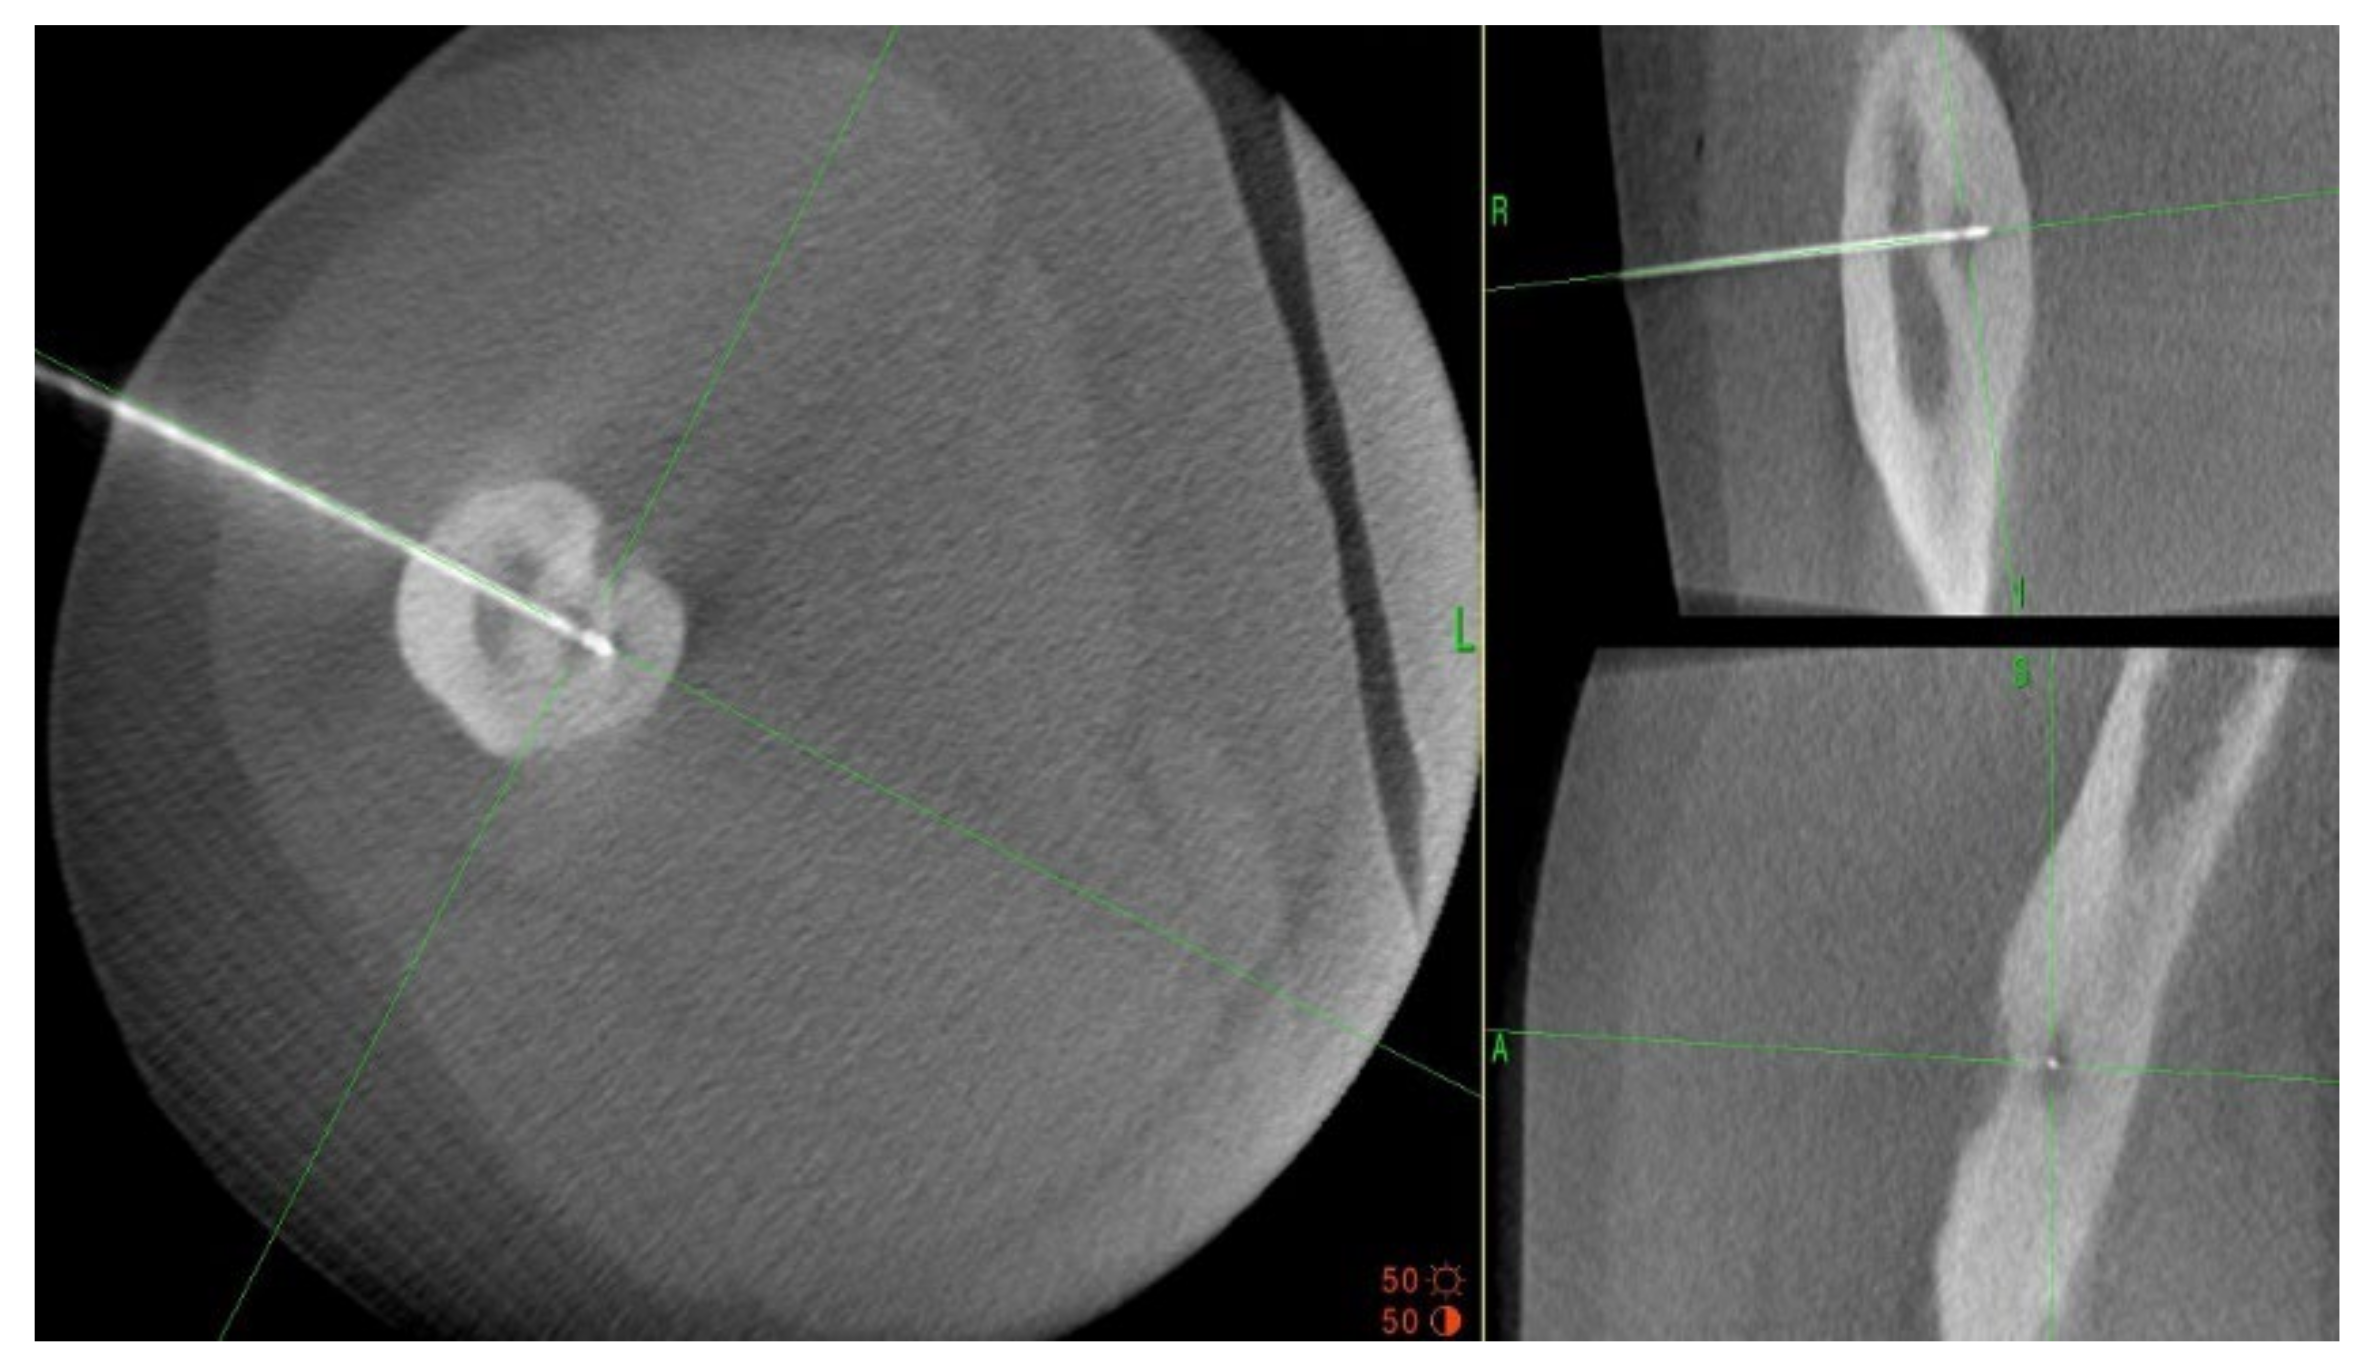

3.1. Case 1: OO Masking as Femoroacetabular Impingement (FAI)

3.2. Case 2: Example of an Incorrect Therapeutic Path of OO

3.4. Case 4: OO Masking as a Fatigue Fracture